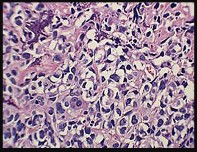

Figures 7a through 7d are the radiograph, MR images, and biopsy specimen of a 35-year-old man who has a painful, slowly enlarging knee mass. Which chromosomal translocation is characteristic of this pathology?

Synovial sarcoma is a soft-tissue sarcoma that usually occurs in young adults. Synovial sarcoma often causes pain, unlike most soft-tissue sarcomas, which generally do not cause pain. Imaging characteristics include soft-tissue calcifications on plain radiographs and a heterogeneous mass that is generally isointense to muscle on T1-weighted images and hyperintense to muscle on T2-weighted images. There are biphasic and monophasic types of synovial sarcoma. The biphasic

type, which is depicted here, has both spindle cell and epithelial components and will stain for both vimentin and cytokeratin. More than 90% of patients with synovial sarcoma have a characteristic genetic translocation of t(X;18), which results in the fusion protein SS18-SSX. This translocation can be stained for use of florescence in situ hybridization technology. t(11;12) is seen in Ewing sarcoma. T(9;22) is seen in extraskeletal myxoid chondrosarcoma. t(12;16) is seen in myxoid liposarcoma.